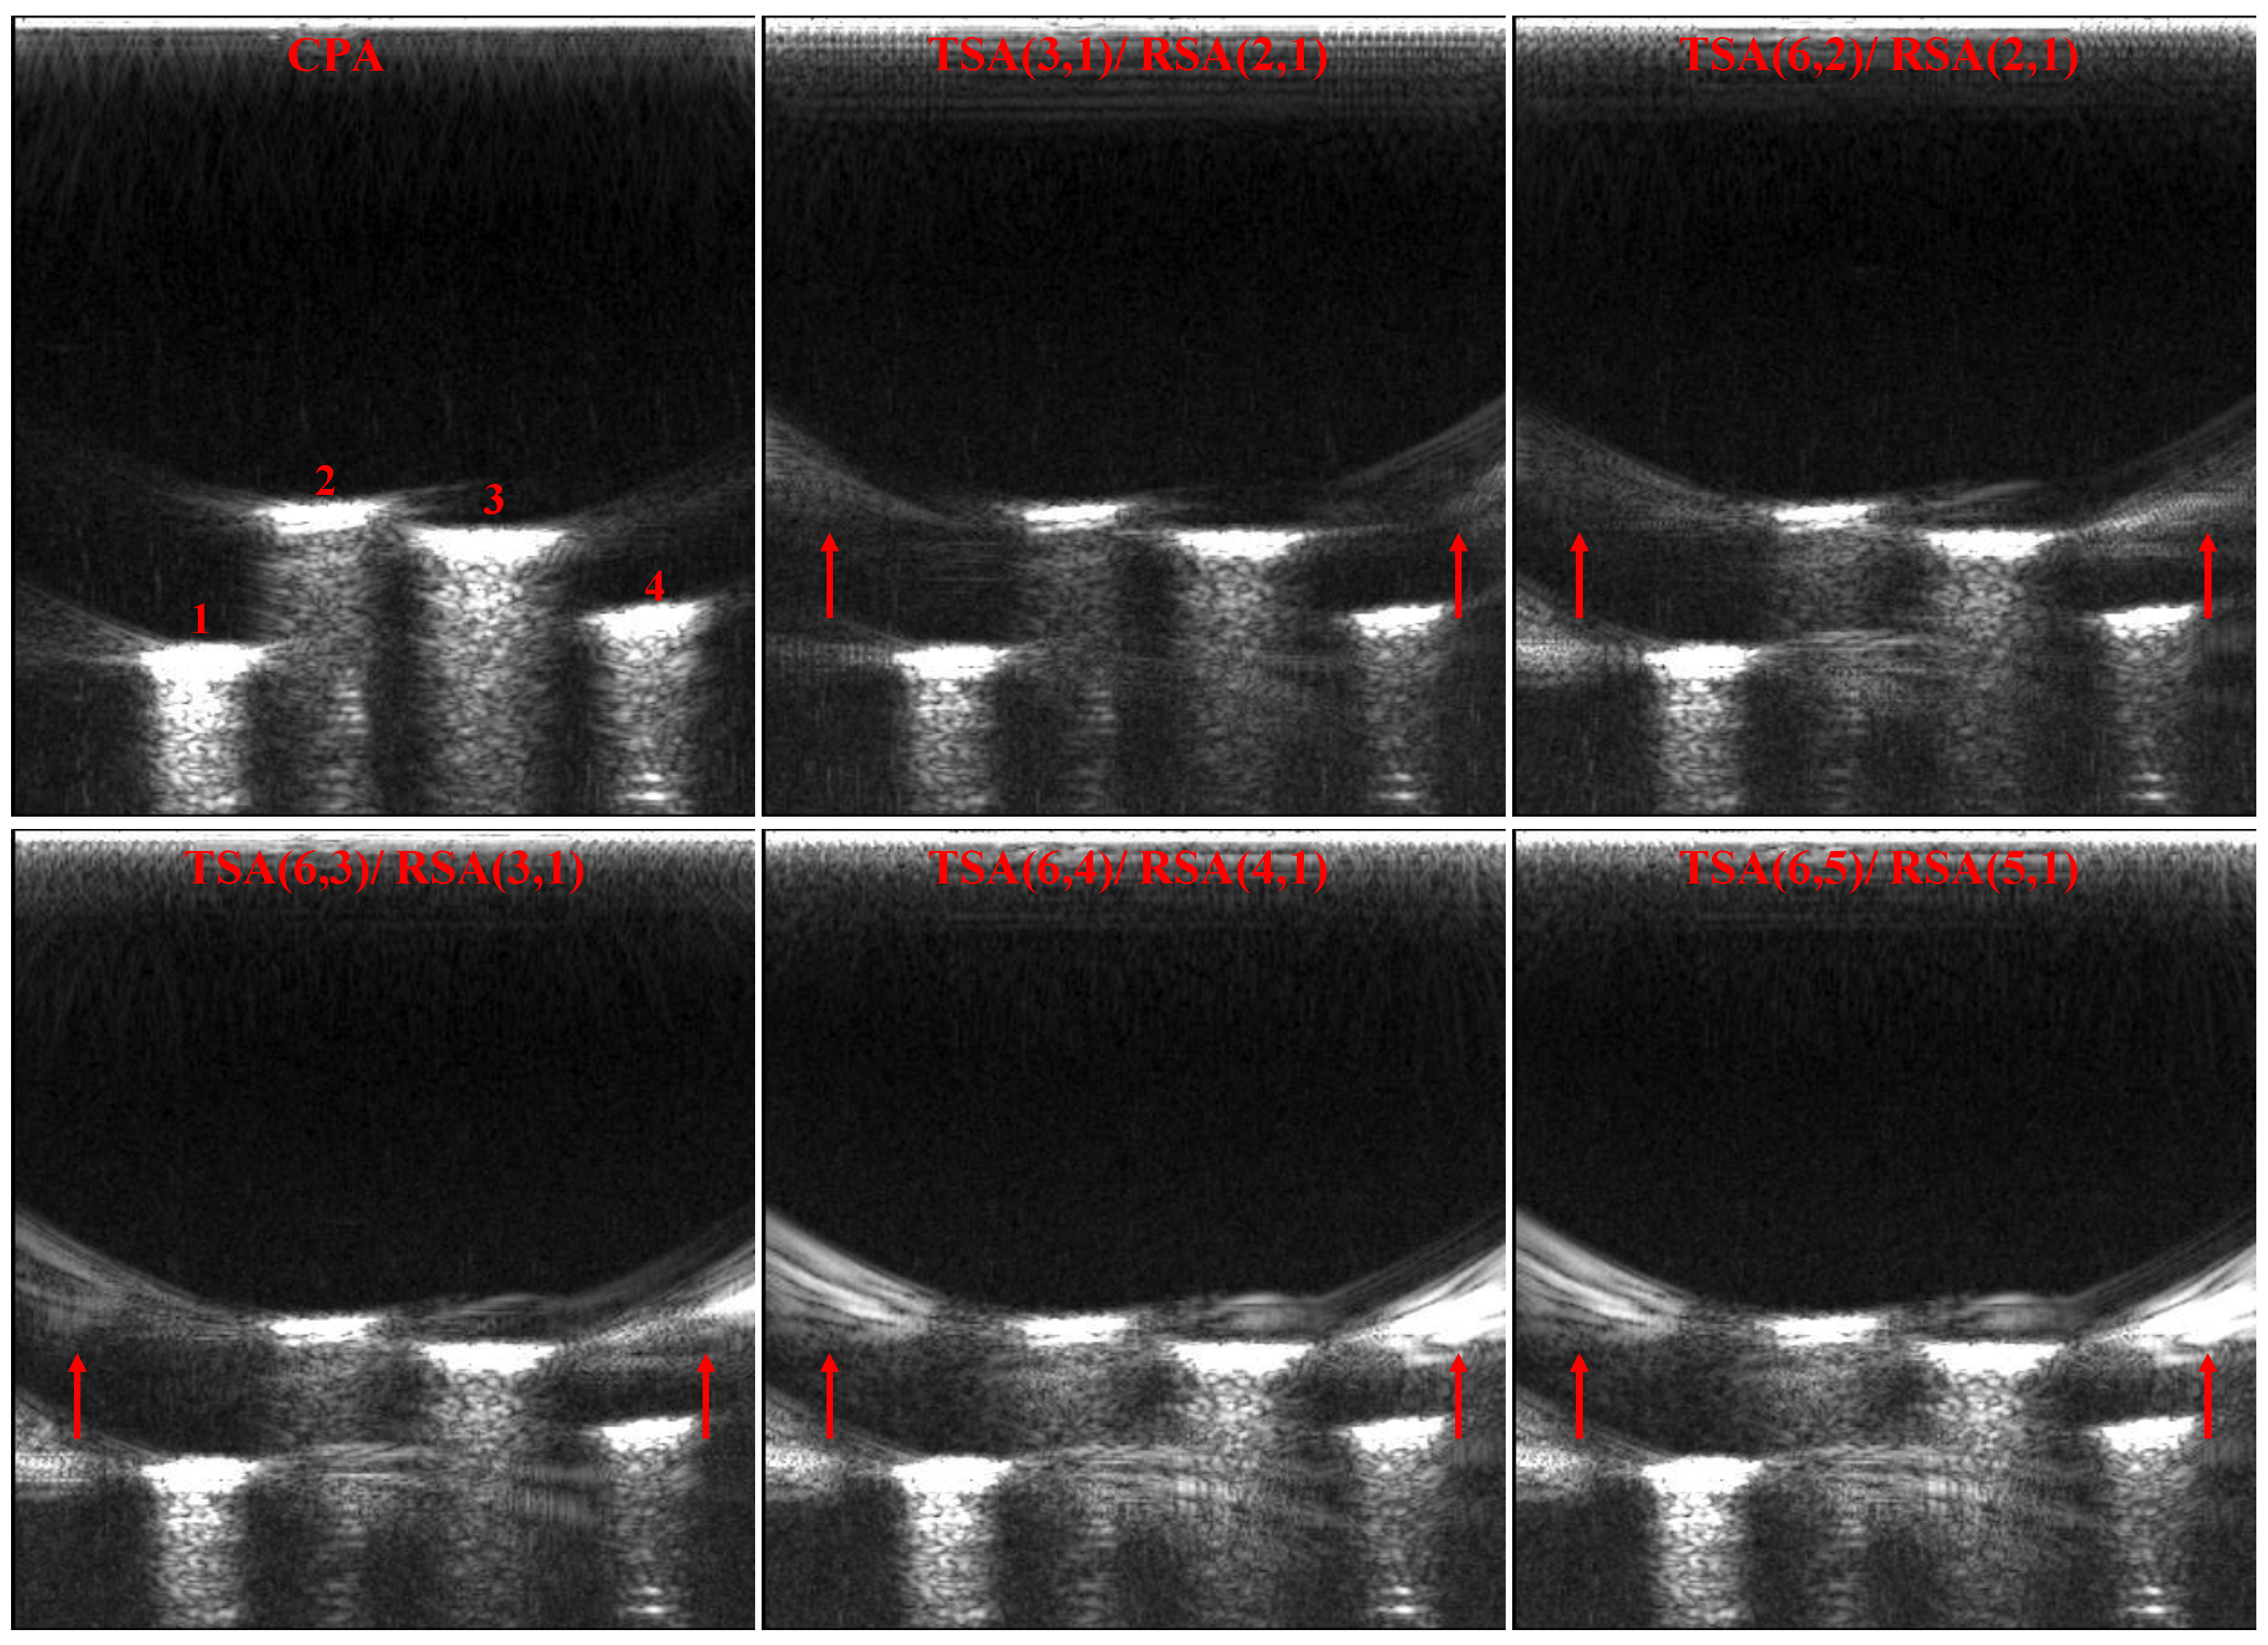

| TSA (3, 1)/RSA (2, 1) | 3795.83 | 34.22 |

| TSA (6, 2)/RSA (2, 1) | 3837.70 | 34.07 |

| TSA (6, 3)/RSA (3, 1) | 3975.23 | 33.92 |

| TSA (6, 4)/RSA (4, 1) | 4115.12 | 33.77 |

| TSA (6, 5)/RSA (5, 1) | 4257.40 | 27.74 |